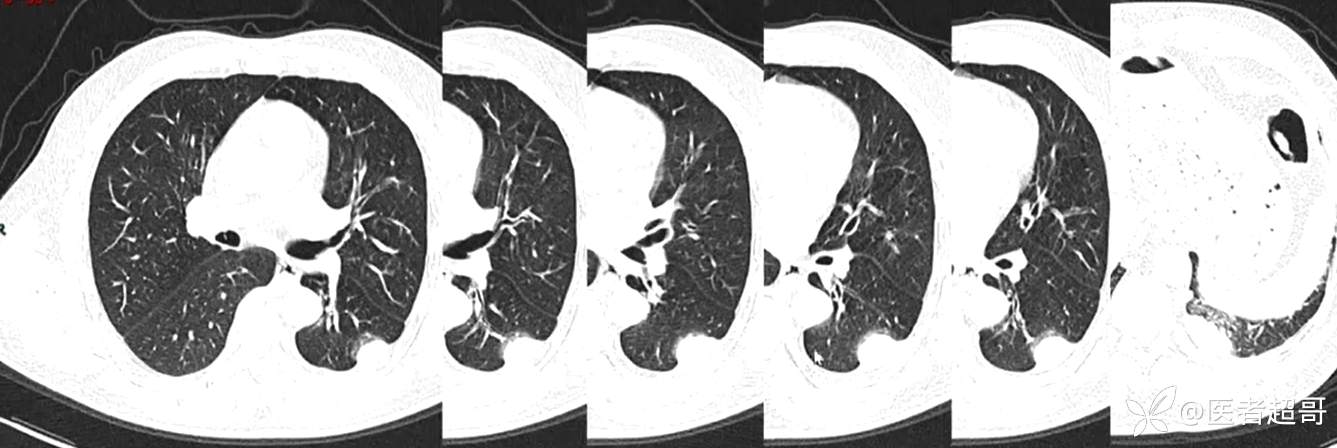

现病史:患者5月前因咳嗽、咳痰于当地医院就诊,完善胸部CT提示:胸膜多发占位,期间患者无胸闷、气紧、咳嗽、咳痰、心慌等不适,患者于我院门诊行胸部CT提示:左下胸膜增厚并见多个软组织密度结节影局限性凸起,较大者大小约3.5x2.2cm,增强扫描呈持续性轻度强化,考虑肿瘤性病变可能性大;门诊遂以:胸膜肿瘤收入我科。